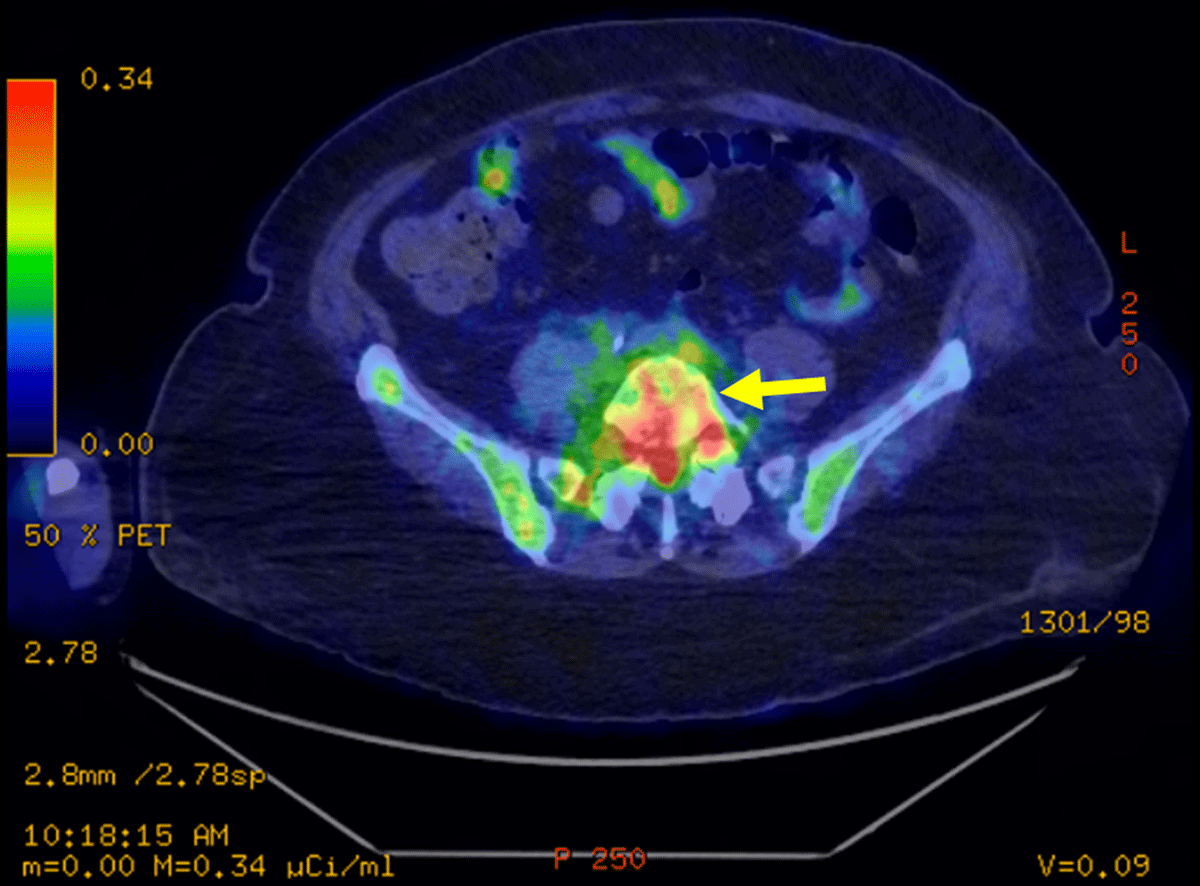

Figure 4

Transverse FDG PET-CT: PET-CT showing hyperfixation of L5-S1 disk.